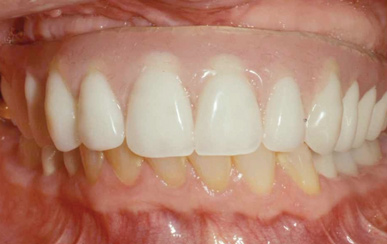

Fig 7. Existing dentition was sound periodontally and reasonably esthetic.

Figure 7